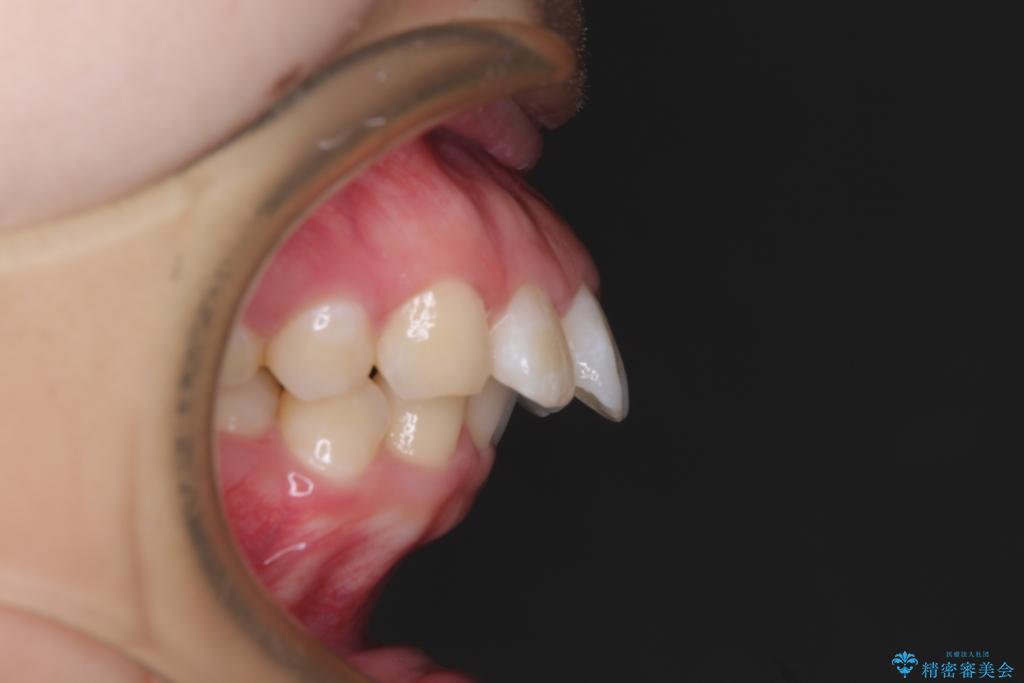

- 上顎前歯が飛び出していて唇がうまく閉じられないとのことで来院された患者様です。

くちばしのように前歯が突出していたため、口元を積極的に引っ込めるために、上下左右の小臼歯4本を抜歯することとしました。

また、上顎歯列が下顎に対して前方位に位置していたため、補助装置を用いて上顎歯列を後方に移動させ、より積極的に口元を下げるようにしました。